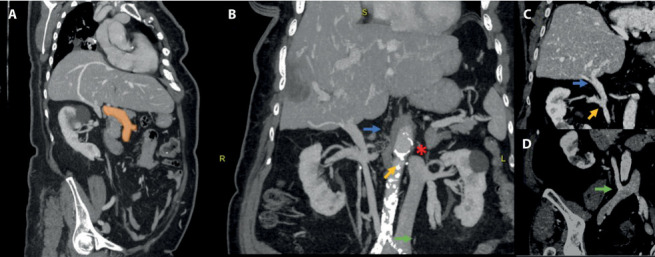

下腔静脉(IVC)中断伴奇静脉/半奇静脉延续是一种极不常见的先天性血管异常,可能存在多种变异。因此,在文献中找到相同的解剖学变体是具有挑战性的。我们报告了一例83岁女性患者的IVC中断伴半奇果和经肝持续的独特病例。该病例通过计算机断层扫描(CT)作为成像模式进行评估,采用多阶段方案,能够准确检测这种复杂的血管异常。本病例报告的目的不仅是介绍这一引人注目的病例,而且从IVC和奇静脉系统的解剖学和胚胎学出发,简要介绍IVC中断的类型,并讨论成像在检测血管异常中的价值。

Inferior vena cava (IVC) interruption with azygos/hemiazygos continuation is an extremely uncommon congenital vascular anomaly, which may present with multiple variants. As a result, it is challenging to find in the literature the same anatomical variant. We report a unique case of an interrupted IVC with hemiazygos and transhepatic continuation in an 83-year-old female patient. The case was evaluated by performing Computed Tomography (CT) as imaging modality, with a multiphase protocol, able to detect accurately this complex vascular anomaly. The purpose of this case report is not only to present this remarkable case but also to briefly show the types of interrupted IVC, starting from the anatomy and the embryology of the IVC and the azygos system, and to discuss the value of imaging in detecting the vascular anomaly.